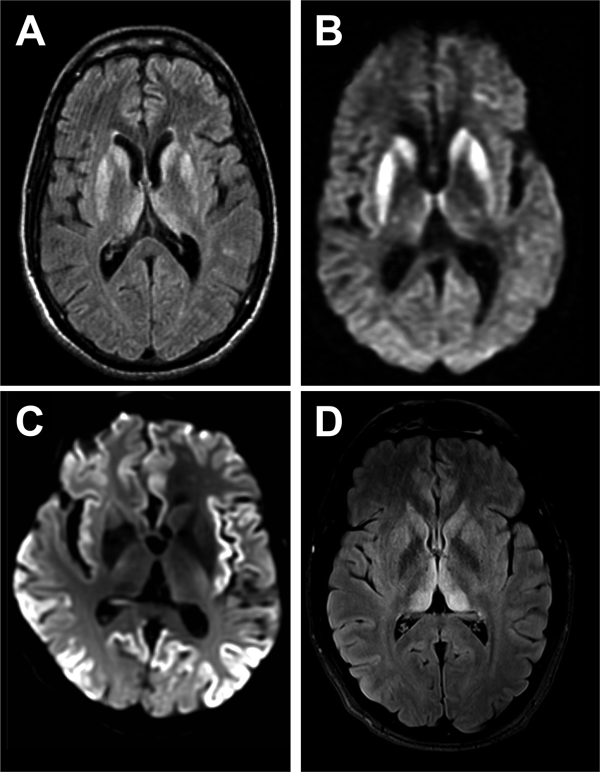

MR imaging of brain is an extremely useful investigation in CJD, because it is readily available at short notice and non-invasive. Classical abnormalities are high signal on diffusion-weighted imaging or FLAIR in the striatum, cerebral cortex and/or thalamus (figure 2). Changes at these three sites may occur in isolation or combination. Cortical signal change is often patchy and extensive but should involve more than one cortical region and areas that are not vulnerable to artefactual signal change (eg, the frontal pole) and should not enhance or show mass effect. Thalamic signal change may be diffuse or have emphasis in dorsal and medial aspects but should not be of greater signal intensity than in the striatum in sporadic CJD. Most units report a sensitivity of MRI>90% in the diagnosis of sporadic CJD. In grey matter, CJD is associated with small vacuoles in neuronal cell bodies, axons or dendrites, which are most probably the pathological substrate for imaging abnormalities. Often, cortical signal change correlates with clinical features, for example, contralateral in the frontal lobe in patients with hemiparesis or occipital cortex signal change in the visual variant of CJD. Post-gadolinium imaging can help identify blood–brain barrier breakdown in lymphoma and neuroinflammatory conditions, which is not seen in CJD.

Figure 2

Typical MRI features of Creutzfeldt-Jakob disease (CJD). (A and B) Sporadic CJD showing typical basal ganglia signal return on fluid-attenuated inversion recovery (FLAIR) (A), which is more obvious on diffusion-weighted sequences (B). (C) Diffusion-weighted imaging sequence showing striking cortical ribboning with normal basal ganglia in sporadic CJD. (D) Variant CJD showing pulvinar sign on the FLAIR sequence.